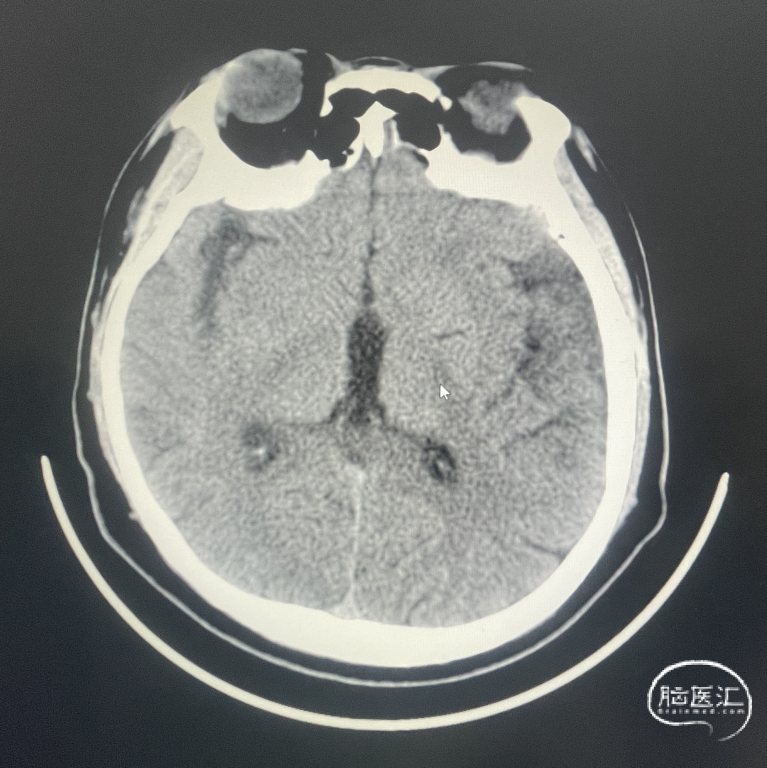

辅助检查:CT见右侧基底节区及右顶叶低密度病灶。

术后CT:术后即刻CT,以及术后24h CT。